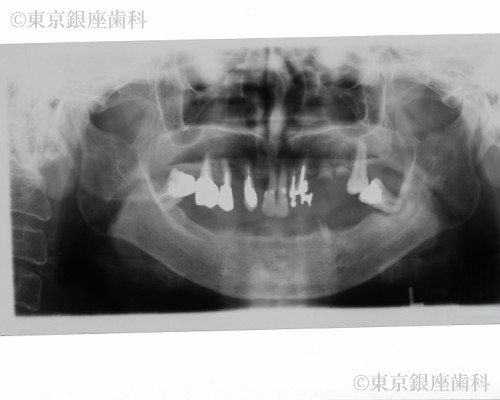

20年経過したインプラントの上部構造を再度新製し快適性を取り戻した80歳代女性の症例

Before

20年前にワンデイインプラントを実施。土台は安定していたが人工歯が経年劣化し再度新製を選択。スペアも作成し将来の負担を軽減した。

上下ワンデイインプラント(補綴再製作)